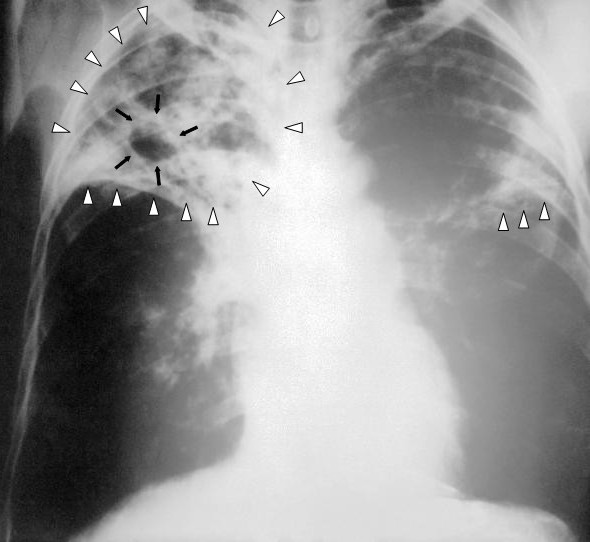

Первое, чем привлекает внимание скелет несчастного парня, это разрастание надкостницы. Выглядит это, как будто кость была покрыта картоном, который потом кто-то исцарапал иглой. Данная патология носит название синдрома Мари-Бамберга. Воспалительный процесс, который деформировал кости несчастного, вызван перманентной гипоксией. Постоянный недостаток кислорода вызывают различные заболевания дыхательной и сердечно-сосудистой систем, включая злокачественные новообразования.

Среди причин развития синдрома Мари-Бамберга есть и туберкулез легких. Эта версия, по мнению ученых, была самой правдоподобной. В пользу данного диагноза свидетельствуют и характерные патологические изменения на ребрах, позвонках и черепе пациента из неолита. Учитывался и молодой возраст покойного, и наличие подобных патологий на скелетах его соплеменников.

Неоспоримые доказательства того, что гипотеза, выдвинутая на основании морфологии повреждений, верна, были получены в XXI веке благодаря современным технологиям. Сделали это ученые из Эдинбургского университета. Из останков жителя доисторического Ходмезевашархей выделили ДНК Mycobacterium tuberculosis. Также были обнаружены липидные биомаркеры инфекции, вызывающей туберкулез легких. Результаты исследования можно найти в октябрьском номере журнала PLOS ONE за 2013 год.